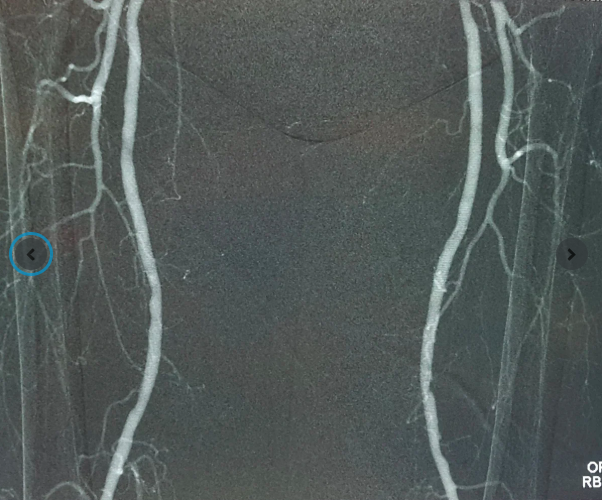

Kết quả siêu âm và chụp mạch tại FV cho thấy động mạch chậu phải bị tắc hoàn toàn đoạn dài, hẹp nặng động mạch chậu trái, động mạch chân phải bị tắc nghẽn hoàn toàn, động mạch chân trái tắc trên 90%. Máu từ tim gần như không xuống được hai chân – đây chính là lý do khiến ngón chân bị hoại tử và tình trạng đau nhức liên tục các ngón chân phải.

Với hệ thống Angiodroid, khí CO₂ tinh khiết được bơm vào mạch máu, thay thế thuốc cản quang truyền thống, vẫn cho hình ảnh X-quang sắc nét và đồng thời đảm bảo an toàn cho thận. Đây là công nghệ đang được nhiều trung tâm y tế tiên tiến trên thế giới ứng dụng, nay lần đầu có mặt tại Việt Nam.

Ca phẫu thuật can thiệp mạch cho ông Đ. diễn ra trong phòng Cathlab với sự hỗ trợ của máy chụp mạch bằng khí CO₂ Angiodroid, hệ thống DSA Philips Allura Xper và các dụng cụ cần thiết. Mục tiêu của phẫu thuật là khai thông dòng máu đến được vết thương ở ngón chân, giúp cải thiện tình trạng lành thương cho bệnh nhân.

Ca can thiệp nội mạch sử dụng khí CO₂ để chụp mạch và phẫu thuật bắc cầu cho bệnh nhân N.V.Đ. được các bác sĩ FV thực hiện thành công